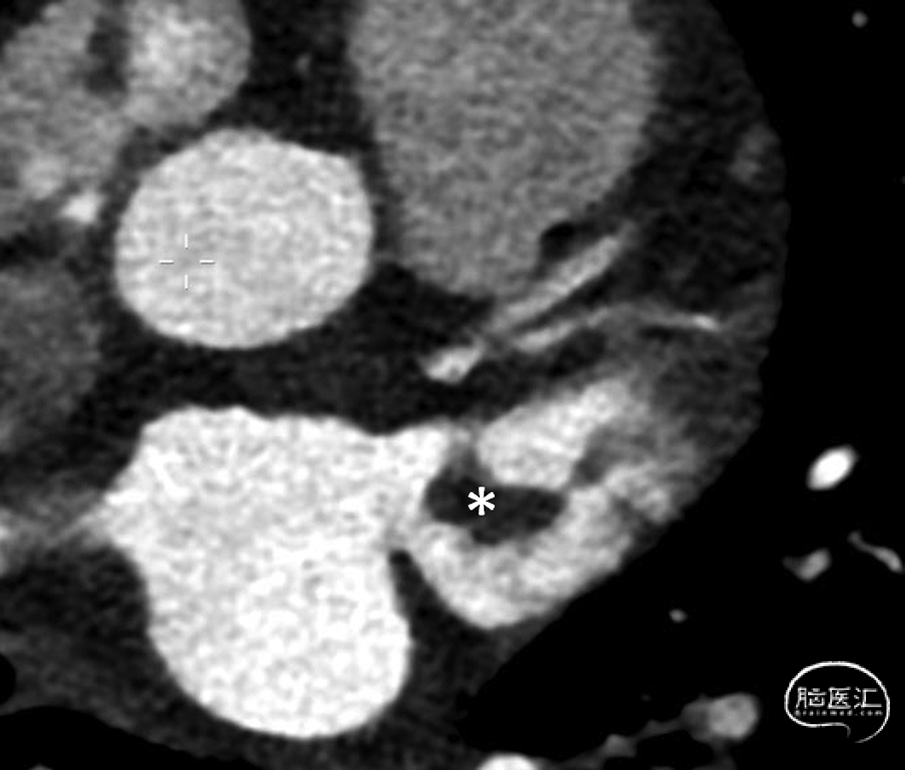

多项研究报告称,左心房内形成的大多数血栓起源于左心耳:例如,在接受心脏手术的房颤患者样本中,75%的左心房血栓来源于此;²³ 在近期发生卒中的房颤患者样本中,这一比例为82%;²⁴ 而在无卒中的非瓣膜性房颤患者中,比例高达91%。²⁵ 无论是经食管超声心动图(图1)还是心脏计算机断层扫描(图2),对于检测左心耳血栓都具有高度的敏感性和特异性。²⁶ 在合并房颤的急性卒中患者中,有相当比例(8%²⁴ 至15%²⁷)的患者可在左心耳内发现血栓。一项近期公布的研究(Sposato等,2024年世界卒中大会)发现,在急性缺血性卒中患者中,将单期相、非门控的计算机断层扫描血管成像范围延伸至心脏,可在8.8%的患者中检出心主动脉血栓,其中最常见的是房颤患者的左心耳血栓。

图2. 心脏计算机断层扫描显示左心耳(LAA)内血栓(*)示例: